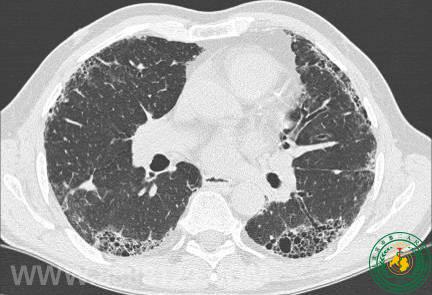

类风湿关节炎,不仅仅是痛那么简单!

类风湿关节炎,不仅仅是痛那么简单!40954